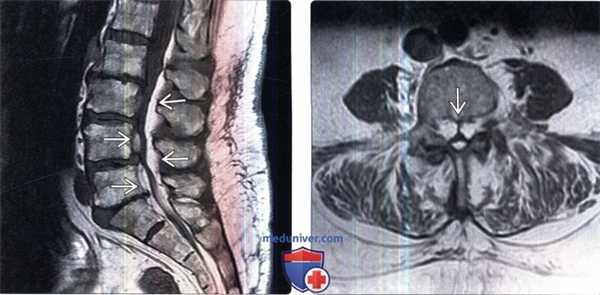

(Слева) На сагиттальном Т1-ВИ определяются признаки жировой перестройки костного мозга нижней половины тела Т5 и целиком тел и задних элементов Т6-Т8 позвонков. Обратите внимание на T9 позвонок, костный мозг которого практически полностью инфильтрирован опухолью.

(Справа) Сагиттальный срез, Т2-ВИ: признаки жировой перестройки костного мозга нижней половины тела Т5 и целиком тел и задних элементов Т6-Т8 позвонков. Костный мозг T9 позвонка инфильтрирован метастазом опухоли.

(Слева) На сагиттальном STIR МР-И у этого же пациента видно, что нормальный костный мозг и измененный в результате облучения костный мозг характеризуются практически одинаковой низкой интенсивностью сигнала, тогда как очаг метастатического поражения характеризуется высокой интенсивностью сигнала.

(Справа) На следующем сагиттальном FS T1-ВИ с КУ отмечается подавление сигнала и отсутствие контрастного усиления подвергшегося облучению и последующей жировой перестройке костного мозга нижней половины тела Т5 и тел и задних элементов Т6-Т8 позвонков. Тело T9 позвонка практически полностью замещено накапливающим контраст метастазом опухоли.